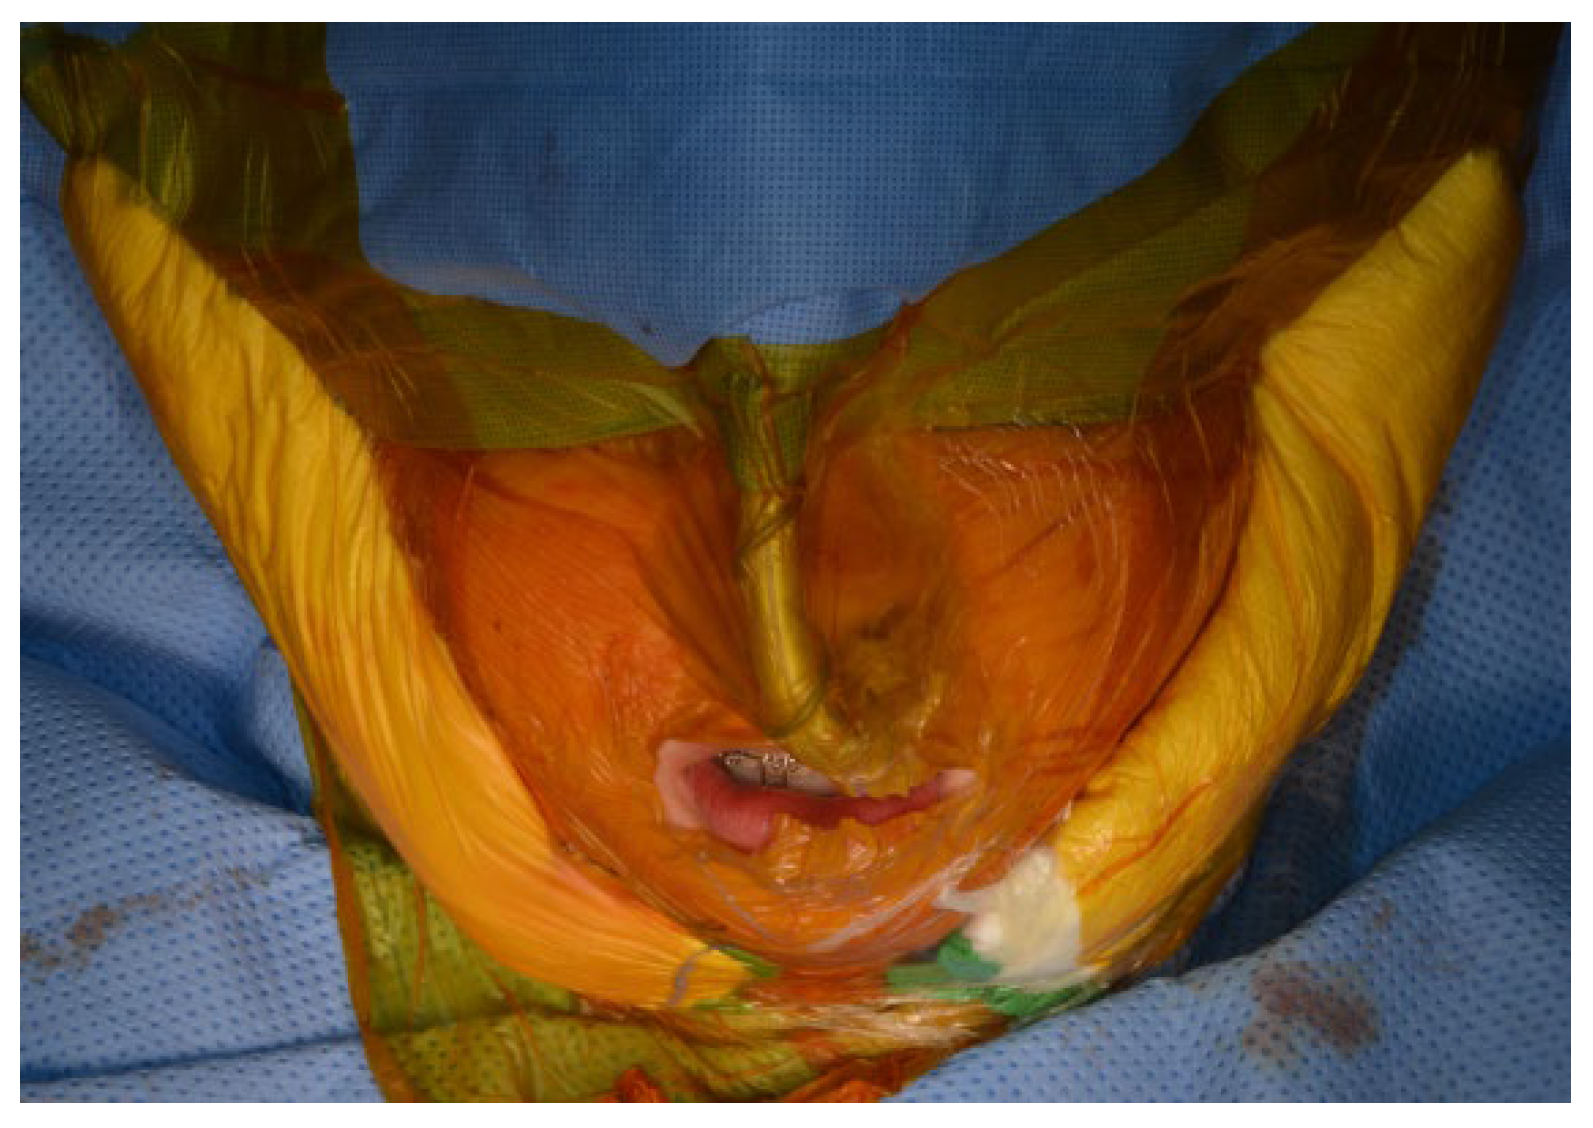

7.8. Maxillomandibular Fixation

After the mandible has been mobilized and the preparation of the TMJ area is completed, the TMJ surgical field is isolated using suitable barriers (Ioban®, Tegaderm®, etc.) to maintain sterility (Figure 9). Additional surgical drapes are placed over previous ones and the exposure is limited to avoid cross-contamination (Figure 10).

Figure 9. TMJ surgical field is isolated using Ioban®.

Figure 10. Additional surgical drapes are placed over previous ones and the exposure is limited to avoid cross-contamination.